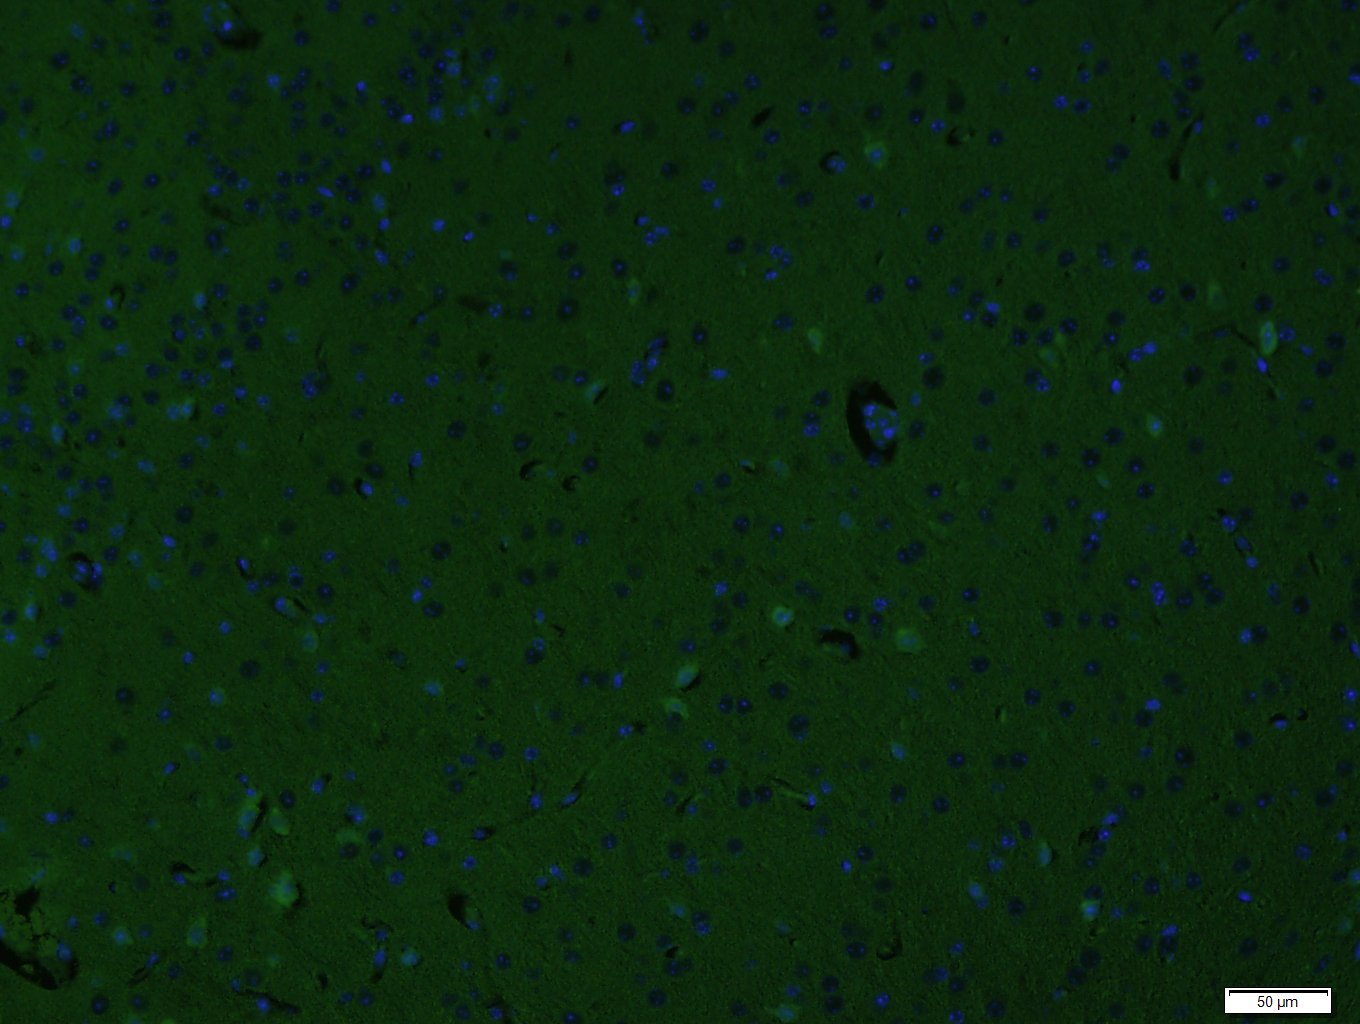

Paraformaldehyde-fixed, paraffin embedded (Mouse brain); Antigen retrieval by boiling in sodium citrate buffer (pH6.0) for 15min; Block endogenous peroxidase by 3% hydrogen peroxide for 20 minutes; Blocking buffer (normal goat serum) at 37°C for 30min; Incubation: Anti-CD34 Antibody, conjugated (bs-0646R-FITC) 1:400, 1.5 hours at 37°C; DAPI (5ug/ml, blue, C-0033) was used to stain the cell nuclei.